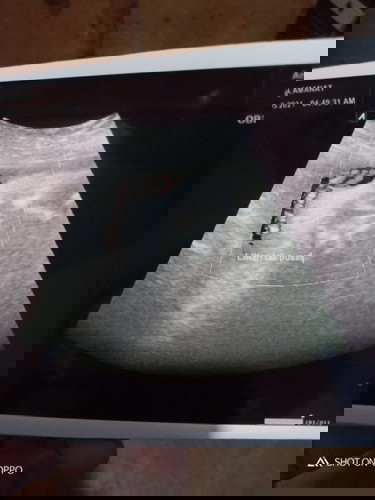

Bayiki terlilit Tali Pusar di 37w6h

Bun, tanyak dong. Gimanayaa supaya Dedenya Lepasin Tali Pusar dilehernya😔 Sumpah aku kefikiran terus sampai Panik banget Yallah😭 Tolong sarannya Bun#seriusnanya

Bunda, dokternya bilang jumlah lilitannya ada brp? Dan lilitannya erat atau longgar Bun? Bunda jgn stress yah, kasih sugesti ke dedek bayinya utk lepasin lilitannya. Banyak yg kasih rekomendasi termasuk dokter utk sering melakukan posisi sujud ibu hamil (bisa cek di youtube posisinya yg baik dan benar), perbanyak jalan pagi dan sore serta berdoa semoga dedek bayinya baik baik dan sehat didalam rahim Bunda ya Bun 🌹